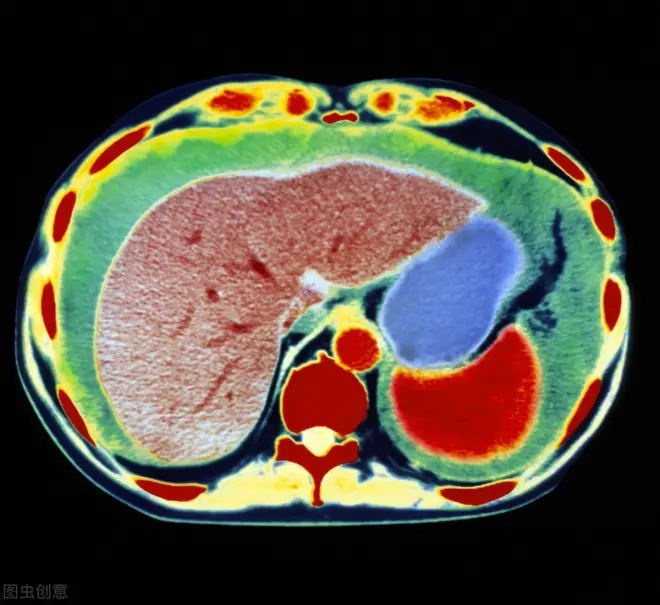

肝腹水反复困扰怎么办?有效防止复发是关键

腹水是肝硬化常见的并发症之一,最近收到很多粉丝的私信,问我腹水经常反反复复是因为什么?是治疗效果不好?还是什么原因?